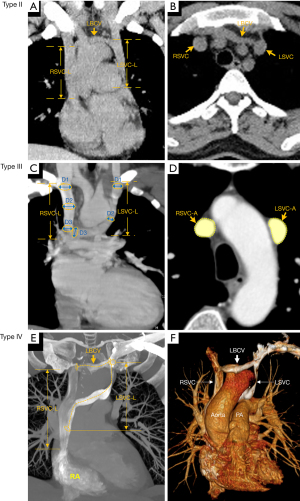

The cases were classified into the following 4 types based on the presence or absence of left brachiocephalic vein (LBCV), the presence or absence of an anastomotic vein bridging the bilateral SVC, and the drainage pattern of the LSVC: (I) type I, DSVC without LBCV, LSVC drainage into the right atrium via the coronary sinus (see Figure 1); (II) type II, DSVC with LBCV, LSVC drainage into the right atrium via the coronary sinus (see Figure 2A,2B); (III) type III, DSVC without LBCV, LSVC drainage into the right atrium via an anastomotic vein bridging the LSVC and RSVC (see Figure 2C,2D); and (IV) type IV, DSVC with LBCV, LSVC drainage into the right atrium via an anastomotic vein (see Figure 2E,2F).

The following quantitative measurements taken from the CT images (see Figure 1): the length of the RSVC (RSVC-L) was measured from the confluence of the left and right brachiocephalic veins (or from the level of the first sternocostal joint on the right if there was no LBCV) to the entrance of the right atrium; the length of the LSVC (LSVC-L) was measured from the level of the LBCV opening (or the level of the first sternocostal joint on the left if there was no LBCV), to either the coronary sinus entrance to the LSVC or the opening of the bilateral SVC anastomosis; the diameter of the bilateral SVC was obtained by calculating the average of the diameter of the proximal, middle and distal segments of the bilateral SVC at the best display slice; the area of the bilateral SVC was measured at the third segment, from the RSVC to the right atrial entrance; the length of the coronary sinus (CSL) was measured on the oblique coronal plane of the coronary sinus; the diameter of the coronary sinus ostium (CSOD) was measured at the coronary sinus entrance on the oblique sagittal view; and the area of coronary sinus ostium (CSOA) was measured on the transverse orientation of the coronary sinus ostium.

According to our newly proposed classification system, the distribution of the 128 DSVC patients was as follows: type I, 66 of 128 (51.6%) (see Figure 1); type II, 43 of 128 (33.6%) (see Figure 2A,2B); type III, 15 of 128 (11.7%) (see Figure 2C,2D); and type IV, 4 of 128 (3.1%) (see Figure 2E,2F). In the majority of patients (type I and type II; 85.2%), the LSVC drained into the right atrium via the coronary sinus.